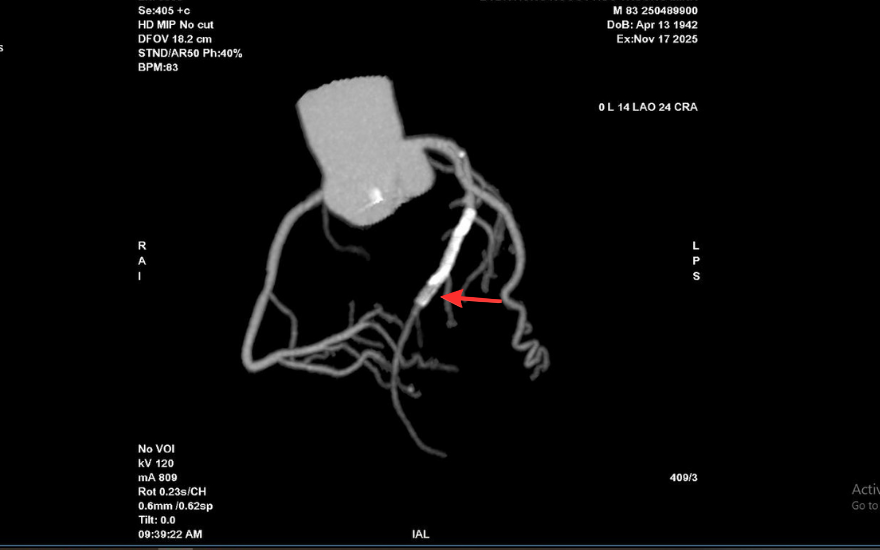

Tại BVĐK Hồng Ngọc, kết quả chụp CT 2560 lát cắt cho thấy tình trạng nghiêm trọng hơn nhiều so với biểu hiện ban đầu: mảng xơ vữa lan rộng gây hẹp nặng đoạn đầu động mạch liên thất trước và gần như làm tắc hoàn toàn lòng stent cũ. Đây là dấu hiệu cho thấy nguy cơ biến chứng tim mạch cấp tính có thể xảy ra bất cứ lúc nào nếu không được can thiệp kịp thời.

Kết quả chụp mạch vành qua da trước can thiệp cho thấy mức độ tổn thương của ông T. nghiêm trọng hơn dự kiến. Lòng stent cũ tái hẹp tới 99%, trong khi đoạn mạch phía trước vị trí đặt stent cũng hẹp khoảng 90%, khiến dòng máu nuôi tim bị chậm đáng kể.